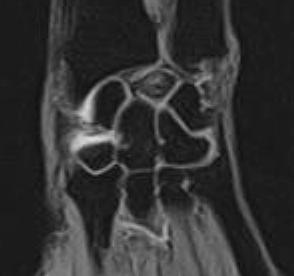

The lunate carpal bone appears hypointense on the T1 Weighted images and heterogeneously hyperintense on the GRASS images. There is slight decrease in the height of the lunate bone with slight elongation of the lunate in it's antero-posterior dimension. Fluid is noted in the region of the scaphoid and trapezium bones.

Stage III:

There is a distal-to-proximal collapse in the coronal plane and elongation in the sagittal plane with proximal migration of the capitate. The absence or presence of scapho-lunate dissociation with rotatory subluxation of the scaphoid divides patients into IIIA and IIIB, respectively. Rotation of the scaphoid may be accompanied by ulnar deviation of the triquetrum. Articular cartilage degeneration may be seen. Carpal fusions may occur.